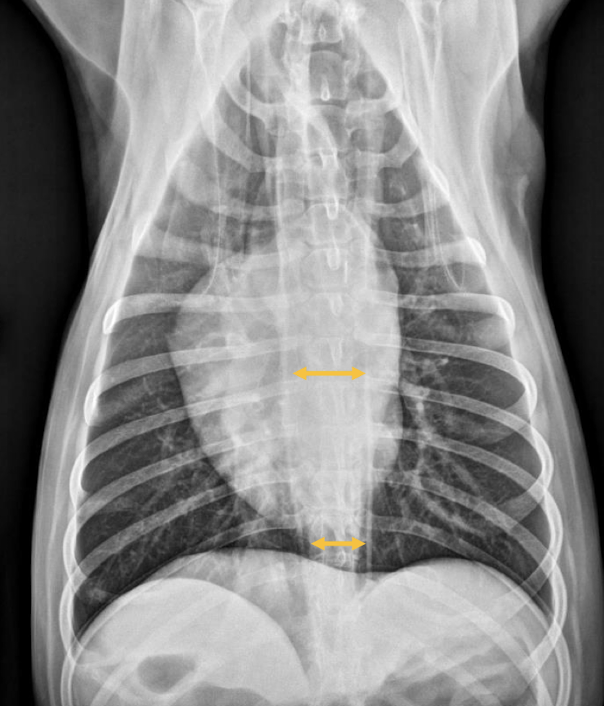

What are radiographic signs of megaesophagus?

Tracheal stripe sign

Esophagus more visible

“V” sign on VD

Esophageal dilation